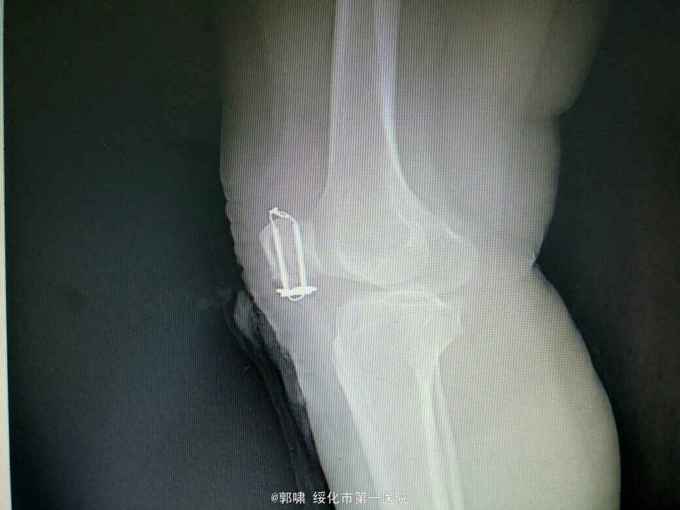

左膝关节摔伤,肿胀,畸形,活动受限一小时。收入院。患者于一小时前滑倒摔伤。当即倒地,左膝关节肿胀,畸形不能行走。门诊拍片示:左膝关节髌骨骨折,断端移位。门诊以左髌骨骨折收入院。

左膝关节肿胀,局部畸形,不能下地行走。浮髌试验阳性。拍片示:左髌骨骨折。

诊断:左髌骨骨折。立即予以腰麻下行切开复位内固定术。术中复位骨折,缝合筋膜,冰水浸泡髌骨爪约10分钟。待髌骨爪变软。选取合适大小的髌骨爪。应用记忆合金髌骨爪内固定。立即用40°温盐水热敷局部。使记忆合金加速抓紧。环抱。缝合爪齿二道,防止脱落。缝合关节囊,韧带组织。术毕。

应用记忆合金髌骨爪内固定髌骨骨折。手术时间基本在20----30分钟内都可以完成。局部损伤小。固定牢靠,确实。患者二个月就可以下地负重活动。具体手术技巧。一是髌骨爪提前用冰盐水侵泡10分钟左右。待记忆合金变软即可使用。二。固定牢靠后立即用40°温盐水热敷。使其快速抓紧。三,缝合爪齿,防脱。四如有粉碎,小的骨块可以缝合筋膜固定。有大骨块,最好环扎钢丝,或穿针固定,有时穿骨隧道钢丝捆扎。效果也不错。只要做到以上几点。安全无忧了!以下是以前做的片子。可以看一看。